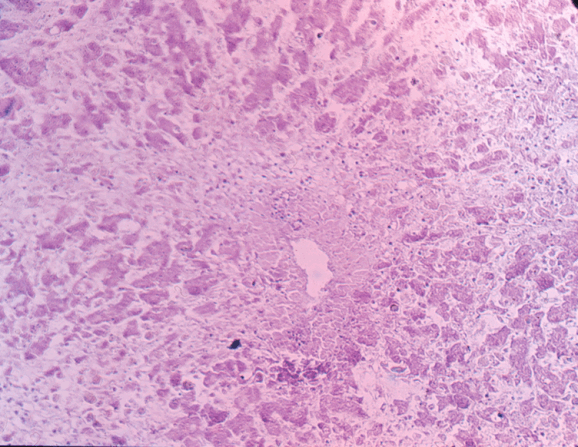

Гемангиома — доброкачественное образование из кровеносных сосудов наследственной природы. Различают простую, или капиллярную, и кавернозную, или пещеристую, гемангиому. Простая гемангиома имеет вид красного или голубоватого пятна, которое при надавливании теряет свою окраску. Возможны сопутствующие поражения кожи. Кавернозная гемангиома состоит из нескольких неодинаковой величины полостей, наполненных венозной кровью и связанных одна с другой анастомозами и соединительнотканными перегородками. Разрастаясь, гемангиомы занимают обширные участки мягких тканей лица, полости рта, языка и др.

Гемангиома — доброкачественное образование из кровеносных сосудов наследственной природы. Различают простую, или капиллярную, и кавернозную, или пещеристую, гемангиому. Простая гемангиома имеет вид красного или голубоватого пятна, которое при надавливании теряет свою окраску. Возможны сопутствующие поражения козки. Кавернозная гемангиома состоит из нескольких неодинаковой величины полостей, наполненных венозной кровью и связанных одна с другой анастомозами и соединительнотканными перегородками. Разрастаясь, гемангиомы занимают обширные участки мягких тканей лица, полости рта, языка и др.